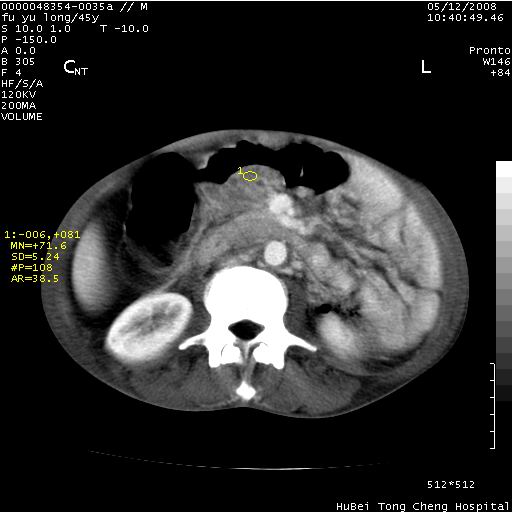

以下是引用医影拾贝在2008-5-30 2:38:00的发言:[br]气肿性胃炎、胃十二指肠溃疡、腹膜炎,考虑穿孔可能性较大

以下是引用lkc8963在2008-5-30 8:44:00的发言:[br]胃窦癌伴网膜(胃结肠韧带)/腹膜及腹膜后淋巴结转移.